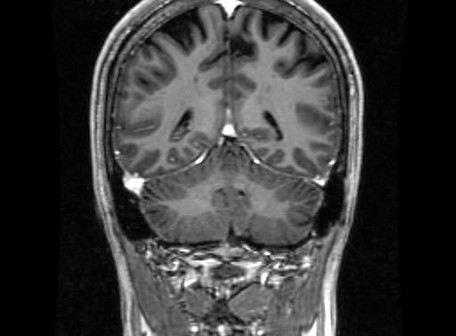

This the anatomical structure of brain. It will will explain about brain planes, brain lobes and cross-sectional of brain anatomy in MRI